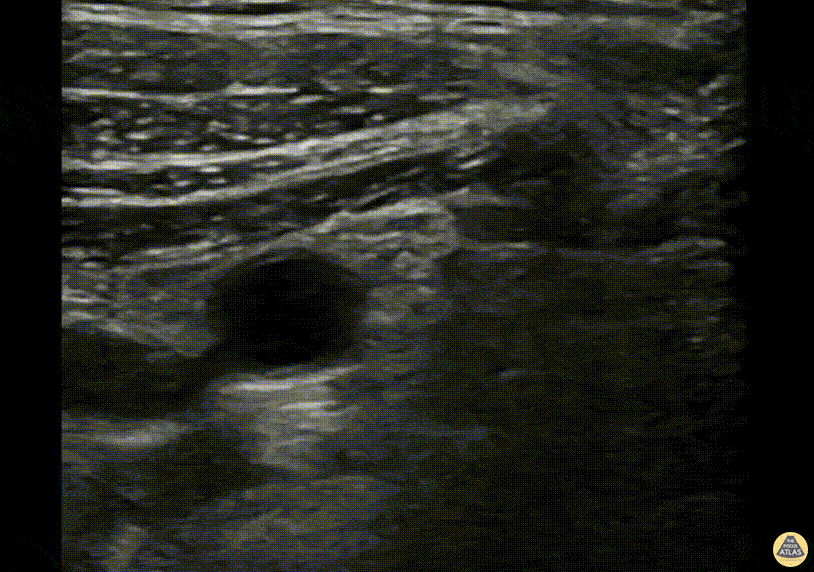

A 71-year-old male presented to the ED one day after a ground level mechanical fall during which he sustained a L shoulder injury. Given his age and initial borderline blood pressures, he received CT images of his chest, abdomen and pelvis which initially revealed a minimally displaced humeral head fracture extending into the greater tuberosity. His workup was ultimately otherwise unremarkable. He was consented for an infraclavicular block for pain control prior to being placed in a cuff and collar sling. The needle can be seen approaching the axillary artery, around which the lateral, posterior and medial cords of the brachial plexus lie anatomically. The needle approach is from cephalad to caudal, with the ultrasound probe placed in the deltopectoral groove. The goal of this block is to deposit anesthetic at the 6 o’clock position relative to the axillary artery. Anesthetic can be seen depositing just superior to the axillary artery, around the 7 o’clock position (screen right). A total of 20 cc of 0.25% bupivicaine with 4 mg of dexamethasone was used. Prior to the block, the patient’s pain score was an 8 out of 10, with significant pain with passive or active range of motion. Shortly after the block, his pain decreased to a 2 and he started ranging his shoulder with minimal discomfort. He was placed in a sling and ultimately stayed in the observation unit for frequent falls and PT/OT evaluation. Dr. Spencer Seballos, PGY-2, Denver Health Emergency Medicine Residency Dr. Fred Milgrim, Ultrasound Fellow, Denver Health Emergency Medicine